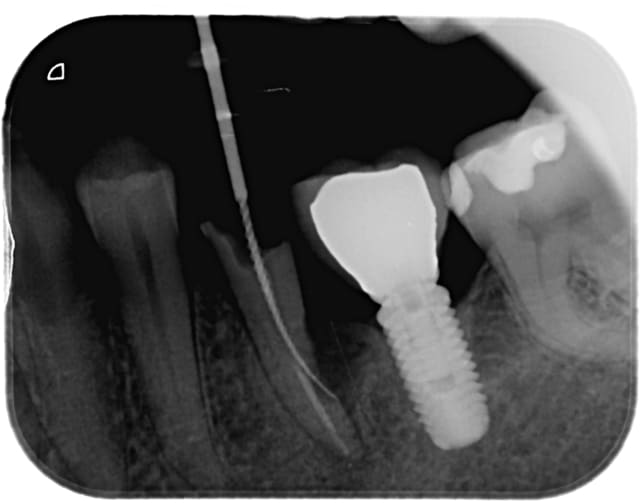

Autre cas avec petite modification dans le protocole pour éviter les mésaventures du cas précédent :

Adulte (dens in dente qui a entrainé la nécrose de la dent)

J'ai placé des éponges hémostatiques au delà de l'apex ce qui permet de créer un matelas plus dense à la limite de la racine et ainsi de condenser plus sereinement le MTA.